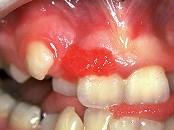

组图是牙龈瘤患者,有关此病的描述不正确的是 ( )

A可能导致牙松动

B可破坏牙槽骨壁

C肿块较局限

D生长较慢

E为恶性病变